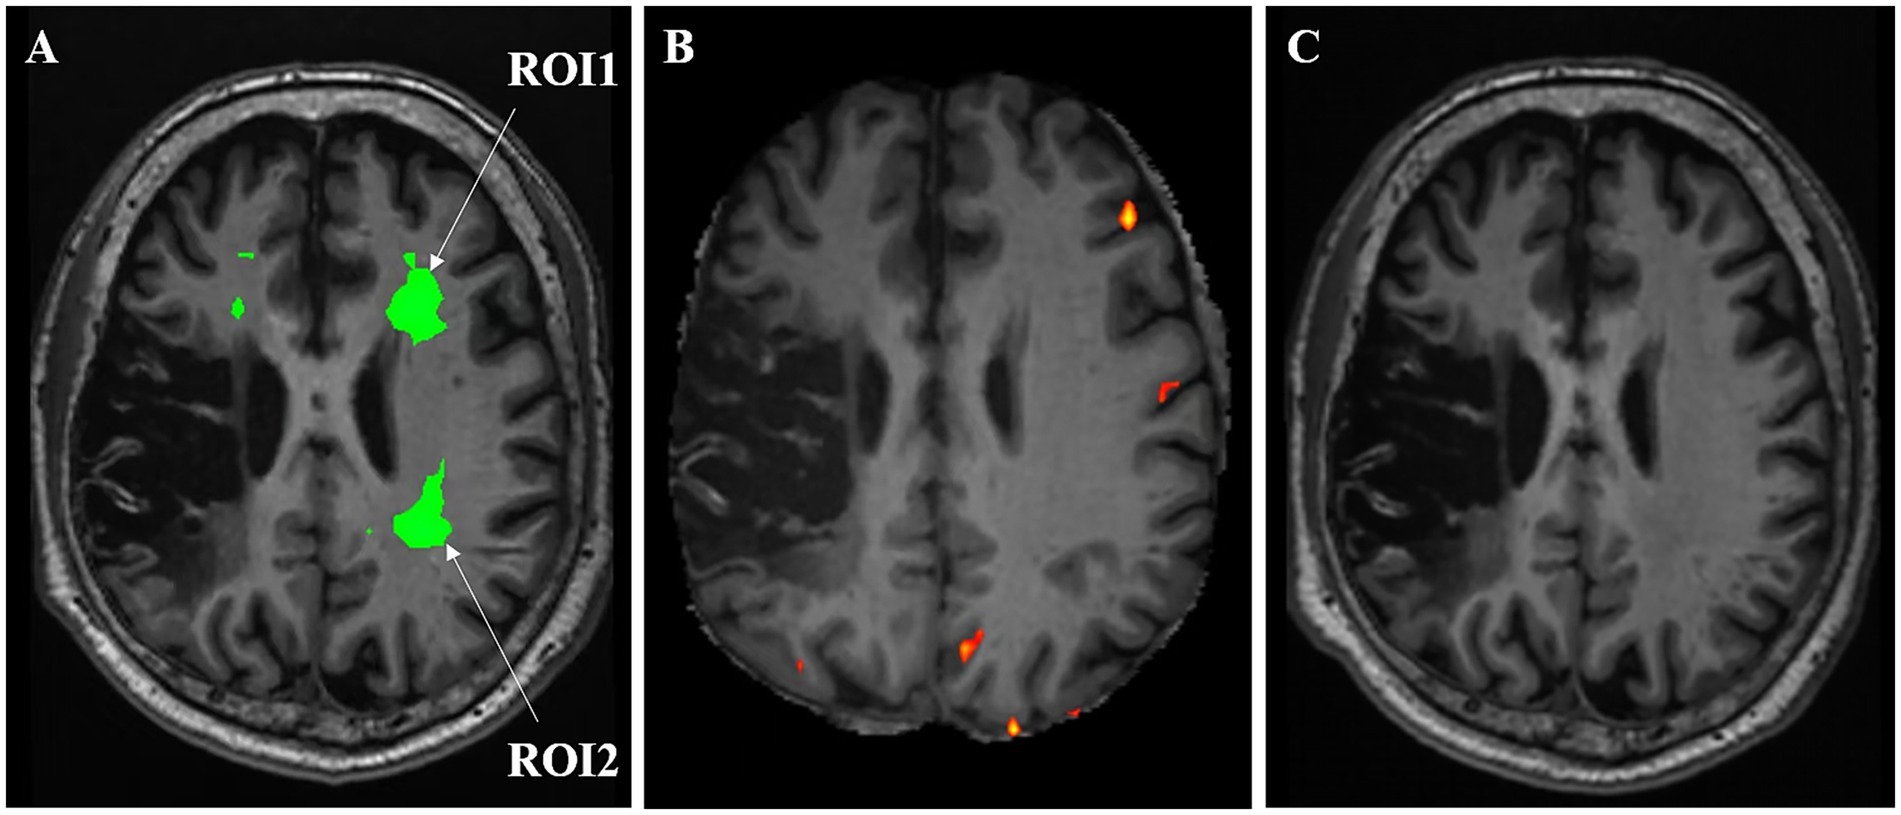

On 31 December (day 1) 2024, blood biochemistry, neuroelectrophysiological, and pain scale assessments were performed (treatment protocol, see Figure 1). On 1 January 2025, when the patient’s CPSP reached a VAS score of 6, BOLD-fMRI revealed two areas of abnormal signal in the patient’s left cerebral hemisphere: region of interest 1 (ROI1) and region of interest 2 (ROI2). From January 2 to 5, ibuprofen sustained-release tablets 0.3 g twice daily were added as an analgesic adjustment for pain relief. Subsequent cranial BOLD-fMRI showed resolution of the abnormal signals in both ROI1 and ROI2 (see Figure 2). In view of (1) the changes in BOLD-fMRI resulting from painkiller adjustment, (2) our prior animal study demonstrating that tLIFU modulation of the anterior cingulate cortex (ACC) effectively alleviated chronic neuropathic pain in mice (Feng et al., 2021), and (3) the proximity of ROI1 to the ACC on the healthy side (the left ACC), ROI1 was therefore selected as the target for tLIFU treatment in this patient. From January 5 to 18, 2025, gabapentin 0.3 g three times daily was prescribed for pain management without using other analgesics. During this period, the patient’s VAS scores fluctuated between 4 and 6, with daily pain attack frequency of 7–8 episodes, each lasting 30 min to 1 h. To preclude interference effects, no other neuromodulation techniques besides tLIFU have been administered to this patient since November 2024. The first neuromodulation via the tLIFU system (GreenValley BrainTech Medical Technology Corporation) with a single-element focused ultrasonic transducer (F0050A03) was carried out on January 18, 2025 (schematic diagram, see Figure 3). The surface of the transducer is circular, with a focal length of 46.8 mm and a focal spot size of 4.80 mm * 4.70 mm * 38.29 mm. The depth of the focal point can be adjusted by modifying the collimator attached to the transducer. To minimize the impact of the thickness of the human skull, the range of tLIFU fundamental frequency that is often used is 250–650 kHz (Cox et al., 2025). A study from our team indicated that tLIFU stimulation with acoustic pressure below 2 MPa is safe for C57 mice (Wang et al., 2022) and that tLIFU stimulation with a duty cycle (DC) of 1.6%, a spatial-peak time-average intensity (ISPTA) of 113.47 mw/cm2, and a spatial-peak pulse-average intensity (ISPPA) of 28.37 w/cm2 improved social interaction and stereotyped behavior in a boy with autism spectrum disorder (Cheng et al., 2025). Therefore, tLIFU parameters in this study were as follows: the fundamental frequency was 0.5 MHz, the peak-to-peak acoustic pressure was 0.83 MPa, the ISPTA was 53.73 mW/cm2, the ISPPA was 5.37 mW/cm2, the pulse repetition frequency (PRF) was 200 Hz, and the DC was 1%. The therapeutic session lasted 20 min and was administered once daily for 7 consecutive days. Within the duration of tLIFU therapy, the transducer was placed properly relative to the skull, and its focus of the transducer was aligned with the target site and monitored in real-time to achieve precise neuromodulation (Figure 4). The final tLIFU intervention was completed on 24 January 2025, by which time the dose of gabapentin was tapered to 0.3 g twice daily, with no concomitant use of other analgesics or topical analgesic patches. Clinical assessments demonstrated significant reductions in pain, anxiety, and depression symptoms (see Table 1). Electromyography (EMG) revealed normalized motor conduction in the left tibial nerve and restored sensory conduction in the left ulnar nerve. The immediate electroencephalography (EEG) at the end of the last tLIFU treatment detected epileptiform discharges during photic stimulation (see Table 2). No treatment-emergent adverse events were observed during the therapeutic course, such as blood biochemistry abnormalities, neurological deficits, dizziness, headache, or epileptic seizures. Follow-up at 2-month post-tLIFU neuromodulation demonstrated sustained control of pain and emotional symptoms, with no significant exacerbation of limb pain during rehabilitation exercises. Gabapentin maintenance dose remained at 0.3 g twice daily, without supplementary analgesic or topical analgesic patches. No subjectively reported adverse events were documented, and the EEG showed an absence of epileptiform discharges. At 3-month follow-up, the analgesic efficacy persisted with the continued absence of patient-reported adverse events (see Tables 1, 2). At the 150-day follow-up, the patient had discontinued analgesics for 1 month, with no significant worsening observed in pain or mood (see Table 1), and BOLD-fMRI revealed no abnormal signal in ROIs (Figure 2).

Figure 2

Changes in BOLD-fMRI of ROIs before (A) and after (B) analgesic drug adjustment and at day 150 follow-up (C).

One of the key aspects in the treatment of CPSP using non-invasive neuromodulation technology is the selection of modulation targets. A meta-analysis (Lizi et al., 2024) has demonstrated that neuromodulation of the M1 region can reduce pain intensity, while it has limited efficacy in alleviating patients’ anxiety, depression, or improving quality of life. In this case, the CPSP patient experienced exacerbated pain during movement, with pain sensations triggered upon the anticipation of movement initiation, which subsequently led to the development of anxiety and depressive symptoms. It is clear that M1 is not the optimal target for tLIFU intervention. In this case study, pain assessments were conducted before and after adjusting oral analgesic medications. A comparative analysis of brain BOLD-fMRI data acquired before and after analgesic adjustment revealed positive signal changes in two regions (ROI1 and ROI2). The region closer to the ACC of the healthy side, namely ROI1, was selected as the tLIFU target. A review of the literature and consultations with colleagues in radiology and neurology confirmed that the anatomical locations of both ROI1 and ROI2 correspond well to the cingulum bundle (Bubb et al., 2018; Kollenburg et al., 2025). As a key white matter pathway, the cingulum bundle not only interconnects the frontal, parietal, and medial temporal lobes but also links these regions to the subcortical nuclei, serving as a critical hub for integration. The functions of the cingulum bundle are involved in executive control, emotion, pain, and episodic memory (Bubb et al., 2018). Research indicates that structural abnormalities in the cingulum bundle of adolescents with chronic headache are closely associated with post-traumatic stress symptoms and reduced amygdala volume, suggesting that damage to the structure of the cingulum bundle may promote pain chronification (Miller et al., 2021). Furthermore, abnormalities in the white matter of the cingulum bundle are also associated with impaired cognitive function, particularly deficits in attention and executive function (Hermens et al., 2022). In this case, the primary reasons for selecting the cingulum bundle on the healthy side as the target were not only because the abnormal signal area identified by BOLD-fMRI was located there but also because of our considerations regarding the compromised structural integrity of the functional brain areas on the affected hemisphere and the safety issue of tLIFU neuromodulation on that side. Therefore, the cingulum bundle on the healthy side was deemed an appropriate choice. A possible explanation for why modulating the healthy side (left) cingulum bundle significantly alleviated the pain on the patient’s paralyzed side is inter-hemispheric inhibition. According to the current understanding, the role of inter-hemispheric inhibition is to support contrast-enhancing and integrative functions by co-opting the capacities of the two cerebral hemispheres than to permit the suppression of one hemisphere by another (Carson, 2020). Therefore, it is possible to influence the function of the ipsilateral body by regulating the functional area in one hemisphere. Such examples can be found in neuromodulations. Verin and Leroi (2009) demonstrated that repetitive TMS on the hemisphere of the healthy side of patients with poststroke dysphagia, which resulted in the improvement of swallowing coordination. Another study from Park et al. (2013) also highlights the benefits of 5 Hz high-frequency repetitive TMS on the contra-lesional pharyngeal motor cortex for post-stroke dysphagic patients. Notably, after the application of tLIFU treatment to the left cingulum bundle, a significant alleviation of ipsilateral pain and improvement in mood were observed in the CPSP patient, and the positive outcomes were well-maintained at the 5-month follow-up, by which time the patient had already stopped taking painkillers for 1 month. These findings suggest that tLIFU targeting the cingulum bundle for CPSP treatment·may represent a novel therapeutic attempt in pain management.

As an emerging non-invasive neuromodulation technique, tLIFU has demonstrated significant potential for pain management. In this case, the patient suffered from long-term CPSP, a chronic central neuropathic pain condition that impacts both physiological and psychological wellbeing. Prior pharmacological analgesia and TMS intervention failed to achieve satisfactory outcomes. Consequently, we attempted tLIFU neuromodulation for the purpose of better pain management. At the beginning, we acquired the patient’s cranial BOLD-fMRI when the pain intensity peaked and abnormal signals were observed in ROIs, which were anatomically consistent with the cingulum bundle. Following the analgesic medication adjustment, we repeated the BOLD-fMRI when the pain subsided to its lowest level and the signal abnormality in ROIs disappeared. The tLIFU therapy under the guidance of optical navigation, subsequently directed at ROI1, led to preliminary clinical improvement. This individualized tLIFU therapy achieved preliminary success: the patient reported significant pain reduction at 1-week post-treatment with a reduced dose of painkiller, and the analgesic effects were sustained as revealed by the follow-ups. At the 120-day mark, the patient discontinued analgesics, and at the 150-day follow-up, pain remained controlled, and the region of ROIs exhibited a normalized activity pattern, as revealed by BOLD-fMRI. Additionally, the patient exhibited clinically significant improvement in mood. To our knowledge, this study represents the first case report of tLIFU-based precise therapy for chronic CPSP. However, prospective studies validating the efficacy and safety of varying tLIFU parameters in chronic neuropathic pain patients remain lacking. Future studies are warranted to expand the clinical applications of tLIFU and to benefit a broader patient population.